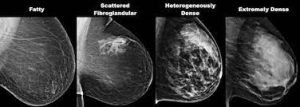

In front of a unique X-ray machine, you will stand. Your breast will be placed on a plastic plate by a technologist. Your breast will be firmly pressed from above by another plate. The breast will be held still during the X-ray by the plates’ ability to flatten it. There will be some strain on you. To create a side view of the breast, repeat these procedures. In the same manner, the other breast will be X-rayed. After that, you’ll have to wait while the technologist reviews the X-rays to make sure no more photographs need to be taken. Remember that the technologist is unable to provide you with the results of your mammography. Because every woman’s breasts are unique, every woman’s mammography may appear slightly different.